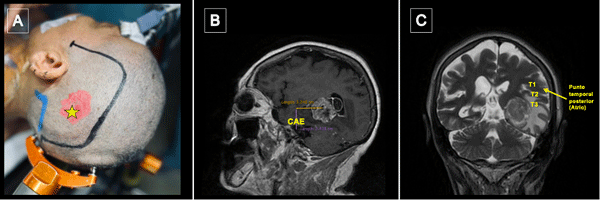

Craneotomía y durotomía

La incisión se centró en el punto temporal posterior (Figura 3), realizándose una herradura frontotemporooccipital izquierda y una cuidadosa hemostasia del colgajo. Craneotomía frontotemporal izquierda. La duramadre fue infiltrada con lidocaína al 1%. Posterior a ello se efectuó una durotomía arciforme con pedículo hacia basal exponiendo el giro temporal superior y medio. Con la paciente despierta se hizo ecografía intraoperatoria para delimitación de los márgenes tumorales, los cuales se identificaron con “tags” (Figura 4).

Figura 3.Punto temporal posterior, posicionamiento. A) Posicionamiento de la cabeza del paciente en cabezal de Mayfield Marcación de incisión centrada en punto temporal posterior (estrella amarilla). B) Se toma como referencia anatómica el conducto auditivo externo (CAE) para medición de punto temporal posterior. C) El punto temporal posterior corresponde topográficamente con el atrio del ventrículo lateral.

Figura 4. Ecografía intraoperatoria y mapeo cortical. A) Utilización de guía ecográfica intraoperatoria para identificar tumor y delimitar sus márgenes (A: Anterior; L: Lateral; M: Medial, P: Posterior). B) Marcación de los límites del tumor con tags de letras (A: Anterior; B: Medial; C: Posterior; D: Inferior) y de las áreas de mapeo positivo con presentación de anomia con dos tags de boca en región posterior de T2. Se expusieron también los giros temporales superior (T1), medio (T2) e inferior (T3) y se optó por corticotomía trans-T2.